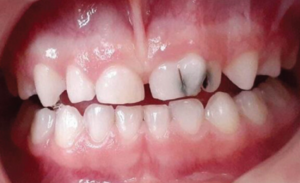

Gemination

Gemination results from a single tooth attempting to divide. It presents as a bifid crown with a single root and root canal.[22] Unlike fusion, gemination does not reduce tooth count.[23] Deep grooves increase caries risk. Treatment may include sealants, restorations, or orthodontic correction.[23]

Clinically, geminated teeth can cause aesthetic concerns, spacing issues, and malocclusion. Depending on its impact, treatment may include sealants, restorations, orthodontic correction, or extraction in severe cases.[23]